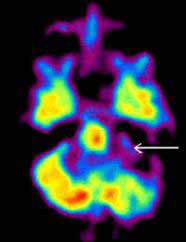

Рис. 2. Позитронная эмиссионная томография при злокачественной шванноме мозжечка. Очаг повышенного накопления 18F-ФДГ у пациента со злокачественной шванномой в левом полушарии мозжечка. Опухоль указана стрелкой (слева). В послеоперационном периоде в левом полушарии мозжечка определяется зона гипометаболизма глюкозы, что свидетельствует о радикальном удалении опухоли. Послеоперационная зона указана стрелкой (справа).